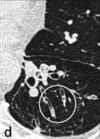

Patrón nodular - TB o cáncer

27

Árbol en brote

28

Localización del patrón nodular

29

Patrón nodular